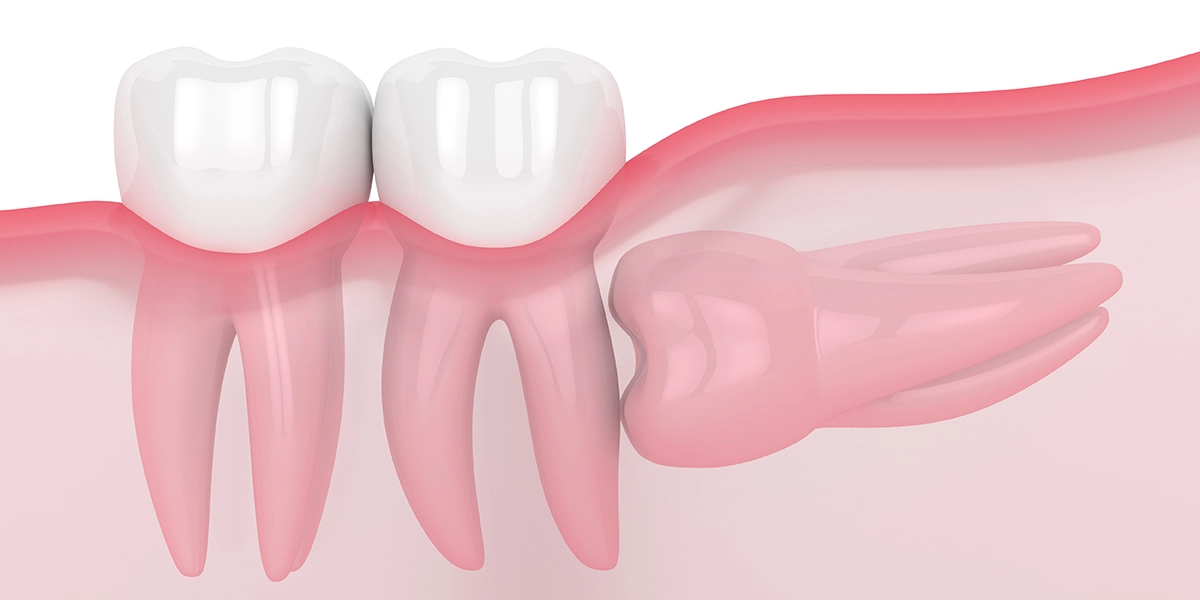

また、横向きに埋まっている親知らずが、手前の歯を押し続けることで、歯並びに影響を与えることがあります。特に、矯正治療後の歯並びが親知らずの力によって乱れてしまうケースも報告されています。歯茎の下に完全に埋まっている親知らずでも、周囲に嚢胞(液体の入った袋)を形成し、顎の骨を圧迫して痛みや腫れを引き起こすこともあります。